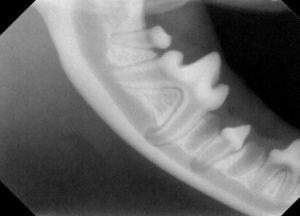

レントゲン検査では、

この様な感じです。

上顎永久犬歯は左右とも本当にありませんでした。

右下顎永久前臼歯を保存するため、乳臼歯を抜歯し、下顎犬歯は外科矯正を実施しました。